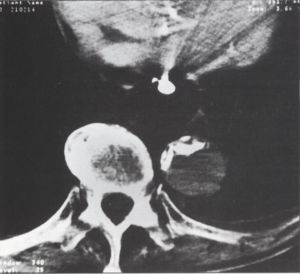

9. ábra.

A nagyított felvételen, a vesék síkja alatt az aorta lumene hipodenz. Benne "C" alakú meszedés a régóta kialakult, kalcifikált felszínű thrombusra utal. Ettől balra a frissen elzáródott szűk lumen. A hasban tág bélkacsok látszanak, folyadéknívóval (ileus).